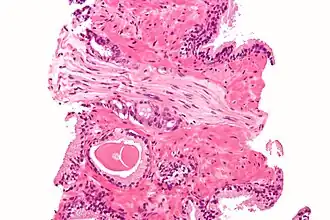

Micrograph showing a prostate cancer (conventional adenocarcinoma) with perineural invasion. H&E stain.

In pathology, perineural invasion, abbreviated PNI, is the invasion of cancer to the space surrounding a nerve. It is common in head and neck cancer, prostate cancer and colorectal cancer.

Unlike perineural spread (PNS), which is defined as gross tumor spread along a larger, typically named nerve that is at least partially distinct from the main tumor mass and can be seen on imaging studies, PNI is defined as tumor cells infiltrating small, unnamed nerves that can only be seen microscopically but not radiologically and are often confined to the main tumor mass. The transition from PNI to PNS is not precisely defined, but PNS is detectable on MRI and may have clinical manifestations that correlate with the affected nerve.[1]